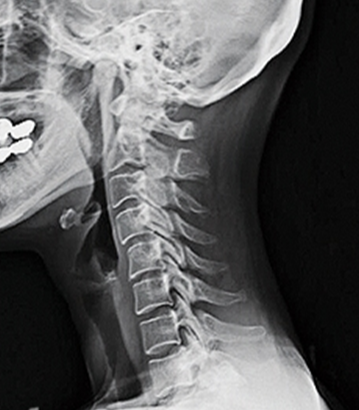

건강한 척추는 척추뼈(척추의 뼈)가 곧고 중립적인 정렬로 겹겹이 쌓인 것으로 구성되며, 경추는 척추의 가장 윗부분을 말합니다.

경추는 처음 7개의 척추체(C1~C7)로 구성되어 있으며 뼈, 추간판, 인대, 힘줄 및 신경의 복잡한 네트워크입니다.

앞서 언급한 바와 같이 목의 자연적인 전만증은 경추를 안쪽으로 C자 모양으로 굽게 하는데, 그 곡률 정도가 20~40도 범위에 속하면 정상적이고 건강한 경추 전만증의 범위로 볼 수 있습니다. 만약 사람이 경추 전만증의 상실을 경험하고 그 정상 범위에 속하지 않는다면 이는 목이 지나치게 곧게 되었다는 것을 의미합니다.